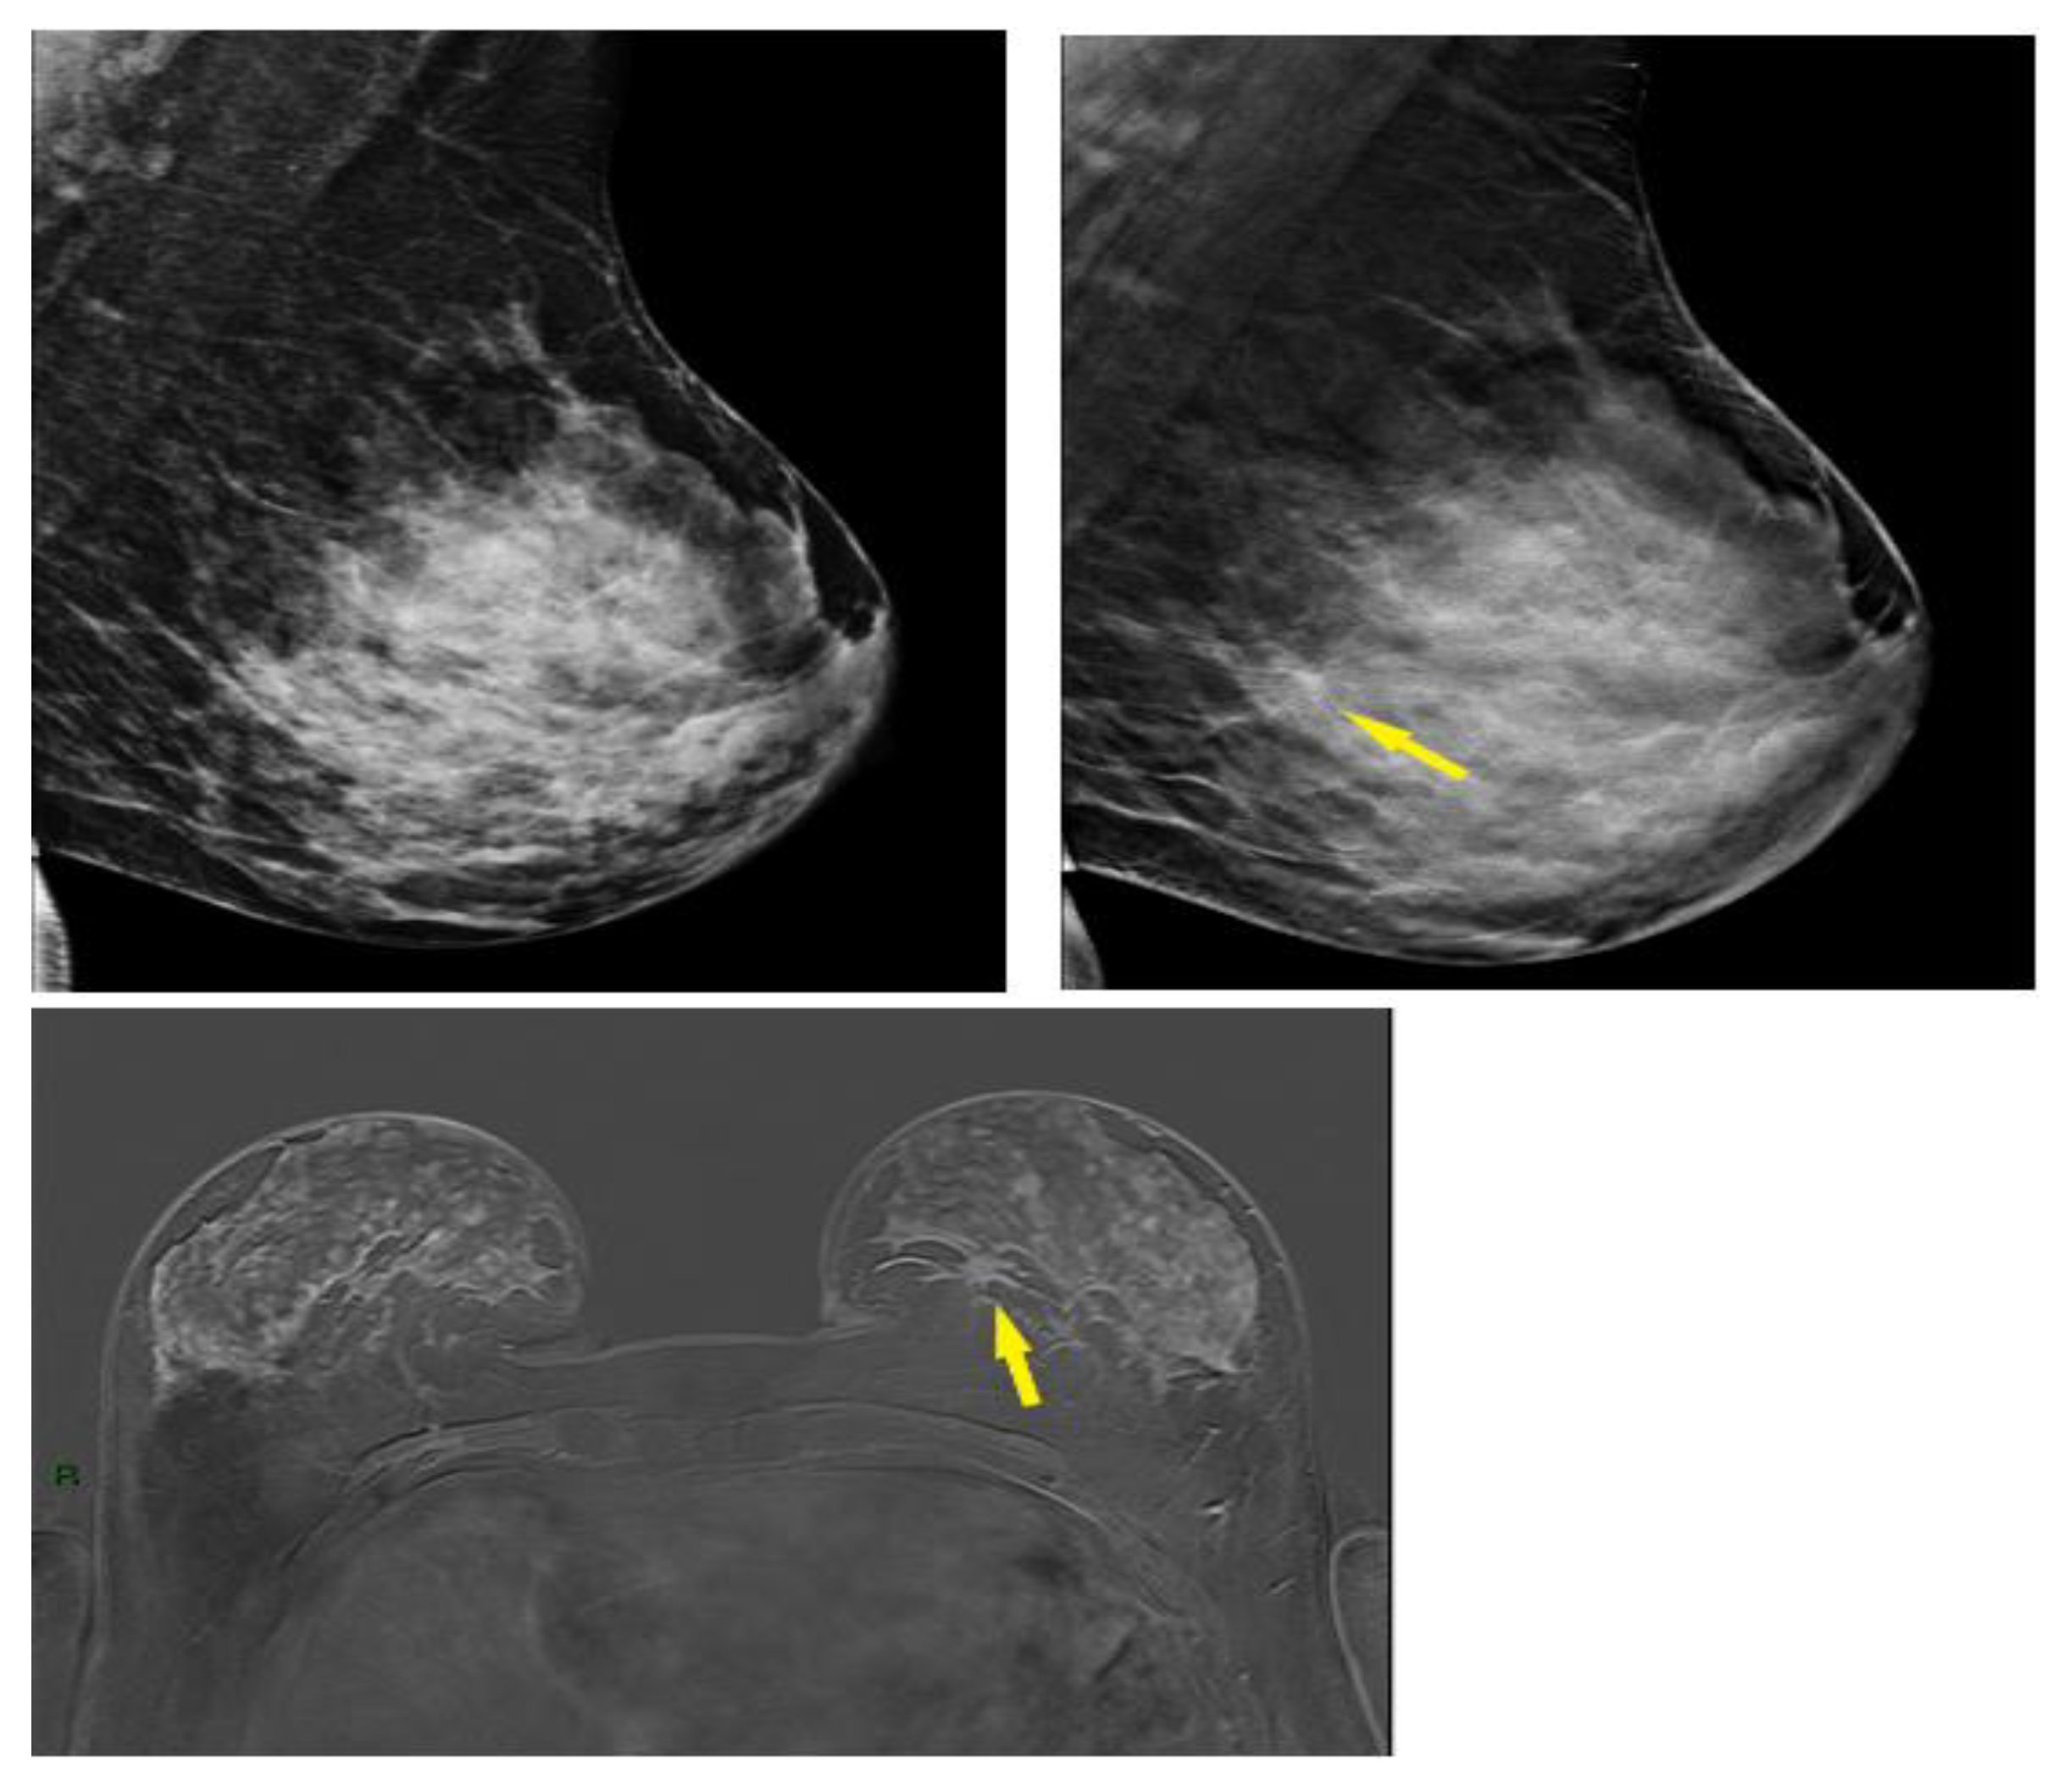

3.4. Selected Interesting Examples from Our Study